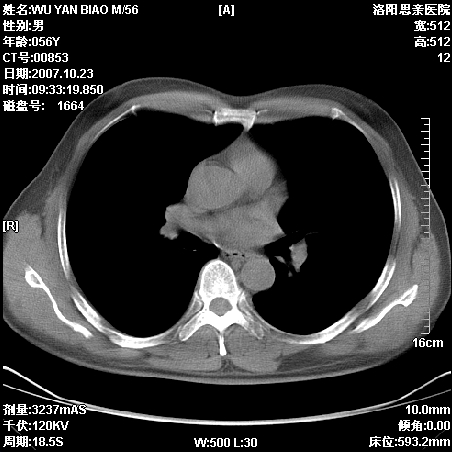

标题: CT10160:M56Y,体检发现,病人无不适,病人随访中 [打印本页]

标题: CT10160:M56Y,体检发现,病人无不适,病人随访中

后上纵隔占位,与肺交界清,宽基底附着脊柱,密度均匀,局部骨质无明确改变.

考虑;神经源性肿瘤,---起源交感n链?,不除外肠源性囊肿.

后纵隔神经原性肿瘤可能性大,孤立性胸膜间皮瘤待排.

请战友们分析一下,有没有局限性胸腔积液的可能?

支持后纵隔神经源性肿瘤!鉴别胸腔纤维瘤。